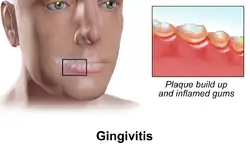

Gingivitis

| Gingivitis | |

| Other names | Ulitis, Early-stage gum disease |

| A severe case of gingivitis | |

Gingivitis is a non-destructive disease that causes inflammation of the gums;[1] ulitis is an alternative term.[2] The most common form of gingivitis, and the most common form of periodontal disease overall, is in response to bacterial biofilms (also called plaque) that are attached to tooth surfaces, termed plaque-induced gingivitis. Most forms of gingivitis are plaque-induced.[3]

While some cases of gingivitis never progress to periodontitis,[4] periodontitis is always preceded by gingivitis.[5]

Gingivitis is reversible with good oral hygiene; however, without treatment, gingivitis can progress to periodontitis, in which the inflammation of the gums results in tissue destruction and bone resorption around the teeth. Periodontitis can ultimately lead to tooth loss.[6]